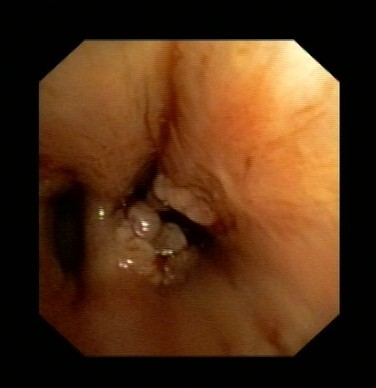

近日,吕先生有门诊收入我呼吸科住院治疗,全体医护人员高度重视,认真讨论病情。我科吴主任仔细看过吕先生的CT片后,观察到右下肺气管内异物,于是决定行支气管镜检查。在气管镜室,吴主任给他做了支气管镜检查,发现吕先生右下肺支气管内卡着一个黑黑的异物,由于时间太久,异物周围已充血水肿,表面有脓苔及坏死物覆盖,清除脓苔及坏死物后,可见异物被肉芽组织紧紧包埋。吴主任成功取出了吕先生气管内异物,并吸出了气管内脓性分泌物。吕先生咳嗽症状立刻改善,行气管镜检查后第二天患者无咳嗽症状,顺利出院。

图表2坏死物吸出后可见异物